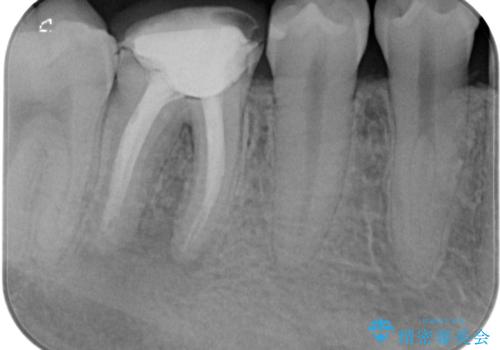

- 右下の奥歯がうずくとのことで来院されました。

根管治療を行った後、セラミックのかぶせ物を装着します。

- 右下6 精密根管治療(大臼歯・リトリートメント):143,000円 土台:22,000円 仮歯:11,000円 ジルコニアクラウン:121,000円 合計297,000円費用は治療当時の料金となります